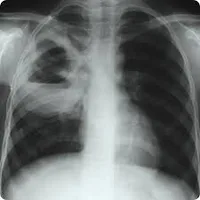

Preevaluación Absceso Pulmonar

1.- Etiología más frecuente de Absceso Pulmonar:

2.- ¿Qué es un absceso pulmonar?

3.- Definición de Absceso Pulmonar Primario:

4.- Definición de absceso pulmonar secundario

5.- ¿Cuándo se amerita drenaje del absceso?